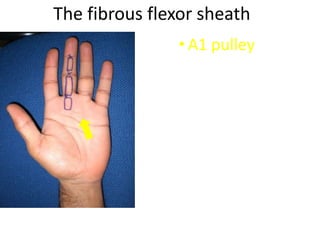

- Naming the bones, joints, tendons, nerves and skin landmarks of the hand and wrist.

- It describes flexor tendon zones, extensor compartments, and pulley system anatomy.